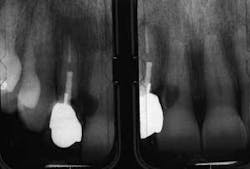

The first patient (see Image 1) was a 63-year-old, white female with no significant medical history. She presented with a buccal abscess between the maxillary right lateral and central incisors. Radiographically, there was evidence of a fracture and decay on the lateral and resorption on the central (see Image 2).

Both teeth were deemed hopeless and slated for extraction. Provisionalization was a challenge as the patient declined wearing a removable appliance, and the adjacent virgin teeth would have required preparation to support a fixed provisional. We elected to extract the teeth, place immediate implants with a narrow-diameter implant in the lateral position (see Image 3), graft between the implant and the extraction site, and place two prefabricated zirconia abutments, which were tightened to 35 Ncm (see Image 4).